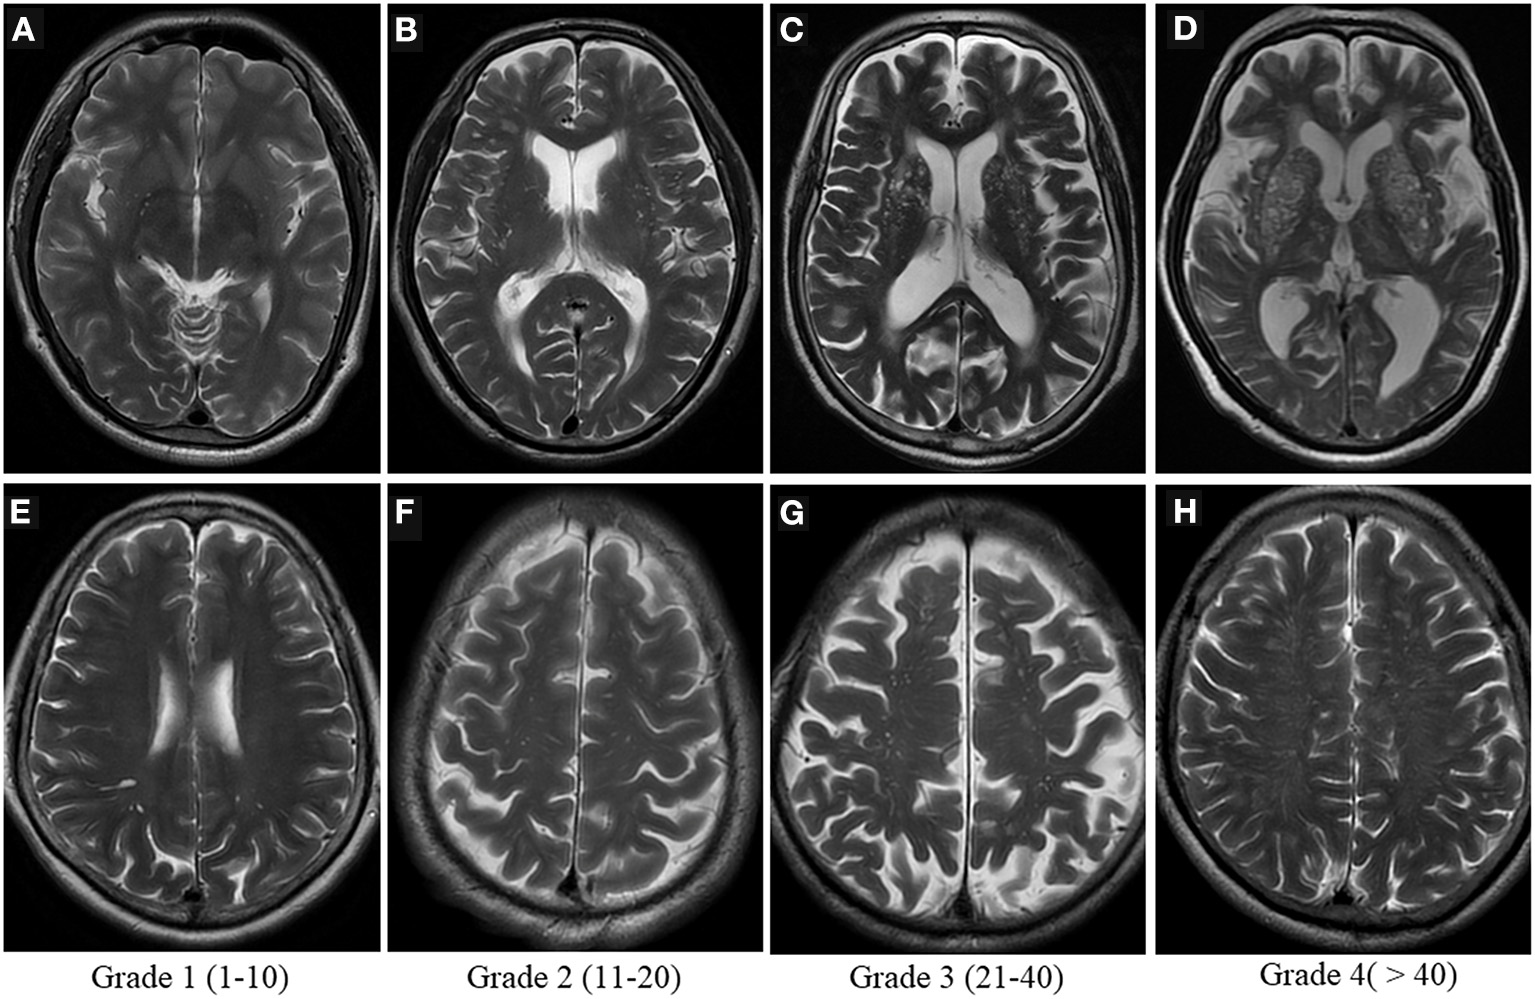

Visual scoring is frequently used to assess the severity of PVS, but there is currently no uniform grading system for radiologists. The most widely used method is Potter scoring. PVS are divided into 0–4 grades (grade 0 none; grade 1 <1–10; grade 2 11–20; grade 3 21–40; grade 4 > 40) according to their number in the BG and centrum semiovale, by counting the side of the cerebral hemisphere with the heavier PVS burden, and 0 to 1 grades for the midbrain according to the presence or absence of PVS (Figure 4) (51). The hippocampus was not involved in the Potter scoring, which has numerous methods of grading. Chinese IntraCranial AtheroSclerosis (CICAS) study group graded the hippocampal region based on the number of PVS as follows: grade 1 <5; grade 2 5–10; grade 3 > 10 (29). Heier classified the PVS based on its diameter as: (mild) grade 1 <2 mm, (moderate) grade 2 2–3 mm, and (severe) grade 3 > 3 mm (52).

Figure 4

Visual scoring of PVS. Potter scoring-Axial T2WI demonstrates the different severity of EPVS in the basal ganglia [top row, (A–D)] and in the centrum semiovale [bottom row, (E–H)], with the corresponding scores (1–4) shown at the bottom.